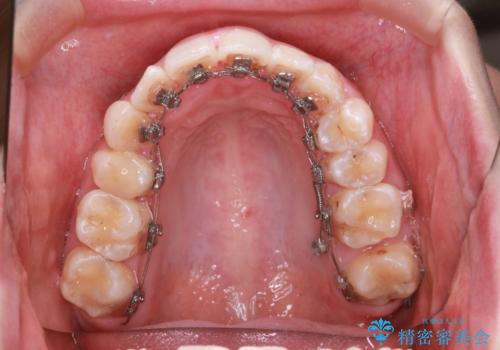

- リンガル装置

- 他院で矯正治療を受けていた患者様が、より理想的な仕上がりを求めて転院されました。主なお悩みは正中(前歯の中心)がズレていることで、歯並び全体をきれいに整えたいとのご希望でした。治療には舌側(裏側)に装置を装着するフルリンガル矯正を採用し、さらにアンカースクリューを用いて奥歯を後方へ移動(遠心移動)させることでスペースを確保し、正中を調整する計画を立てました。

矯正装置を装着し、アンカースクリューを活用しながら奥歯を少しずつ後ろへ動かし、正中を整えていきました。治療には時間がかかりましたが、計画通りに歯を移動させ、バランスの取れた歯並びへと仕上げることができました。裏側矯正のため、見た目を気にすることなく治療を進められた点も、患者様にとって大きなメリットでした。治療後は、「正中がしっかり合って、口元がスッキリした」とご満足いただきました。